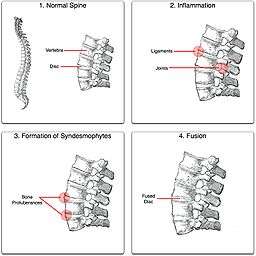

தம்ப முள்ளந்தண்டழல்அல்லது மடங்காதநிலை முதுகெலும்பு வீக்கம் (Ankylosing spondylitis) (AS , என்பது கிரேக்க சொல்லான ஆன்கைலோஸ்- வளைந்த; இஸ்பாண்டிலோஸ் - முதுகெலும்பு) என்ற சொற்களில் இருந்து உருவானது. முன்பு பெச்டெரீவ்ஸ் குறைபாடு (Bekhterev's disease) , பெச்டெரீவ்ஸ் அறிகுறி (Bekhterev syndrome) , மற்றும் மேரி ஸ்ட்ரம்பல் குறைபாடு (Marie-Strümpell disease) என்று அறியப்பட்டது. முதுகெலும்பு வாதத்தின் (spondyloarthritis) ஒருவடிவமான இந்நோய், நாள்பட்ட, வீக்கம் நிறைந்த வாதநோயாகும்[1]. தன்னெதிர்ப்புத் தாக்குதல் இந்நோயில் முக்கியப் பங்குவகிப்பதாகக் கருதப்படுகின்றது[2]. இது முக்கியமாக, முதுகெலும்பில் உள்ள மூட்டுகள் மற்றும் இடுப்புக்கூட்டில் உள்ள திரிக-பின் இடுப்பு மூட்டைப் (sacroiliac joint) பாதிக்கிறது. மேலும், இது முதுகெலும்பு மூட்டுகள் ஒன்றாக சேர்ந்துகொள்ளவும் வழிவகுக்கக்கூடும்.

இந்நோய் தண்டுவட எலும்பு மூட்டு நோய் (spondyloarthropathy) குழுவில் ஒரு நோயாகும். இதில் வலுவான மரபியல் ரீதியான முன்னிணக்கம் காணப்படும். முழுமையாக முதுகெலும்பு கூடிவிடுவதால், முதுகெலும்பு முற்றிலும் விரைத்த மடங்காத தன்மையைப் பெற்று விடும். இந்நிலைக்கு மூங்கில் முதுகெலும்பு என்று பெயர்[3].

தம்ப முள்ளந்தண்டழலைக் கவனிக்காமல் விடும்போதும் அதனுடன் டாக்டிலிட்டிஸ் அல்லது என்திஸ்டிஸ் சேர்ந்து வரும்போதும், குறிப்பாக முதுகெலும்பு வீக்கம் அதிகரிக்கும்போதும் அது சாதாரண மூட்டு பிறழ்வு என்று தவறாக கருதப்படும் வாய்ப்புண்டு. நீண்டகாலம் கவனிக்கப்படாமல் இருந்தால், எலும்புக் குறைபாடு அல்லது எலும்புப்புரை முதுகெலும்பு முன்பின்னாவதால் (anteroposterior) ஏற்படக்கூடும், இதனால் மெல்ல மெல்ல அழுத்த விரிசல்கள் மற்றும் முதுகில் "கூன்" உம் ஏற்படக்கூடும். வளர்ச்சியடைந்த தம்ப முள்ளந்தண்டழலுக்கான பொதுவான அறிகுறிகளாவன, சிண்டெஸ்மோஃபைட்ஸானது எக்ஸ்-கதிரிலும், ஆஸ்டியோபைட்களில் உள்ளது போன்று முதுகெலும்பில், வழக்கத்திற்கு மாறான எலும்பு வளர்ச்சியும் காணப்படும். வெர்டாப்ரே பாரஸ்தீஷியா என்பது நரம்புகளைச் சுற்றியுள்ள திசுக்கள் வீக்கமடைவதால் ஏற்படுகிறது.